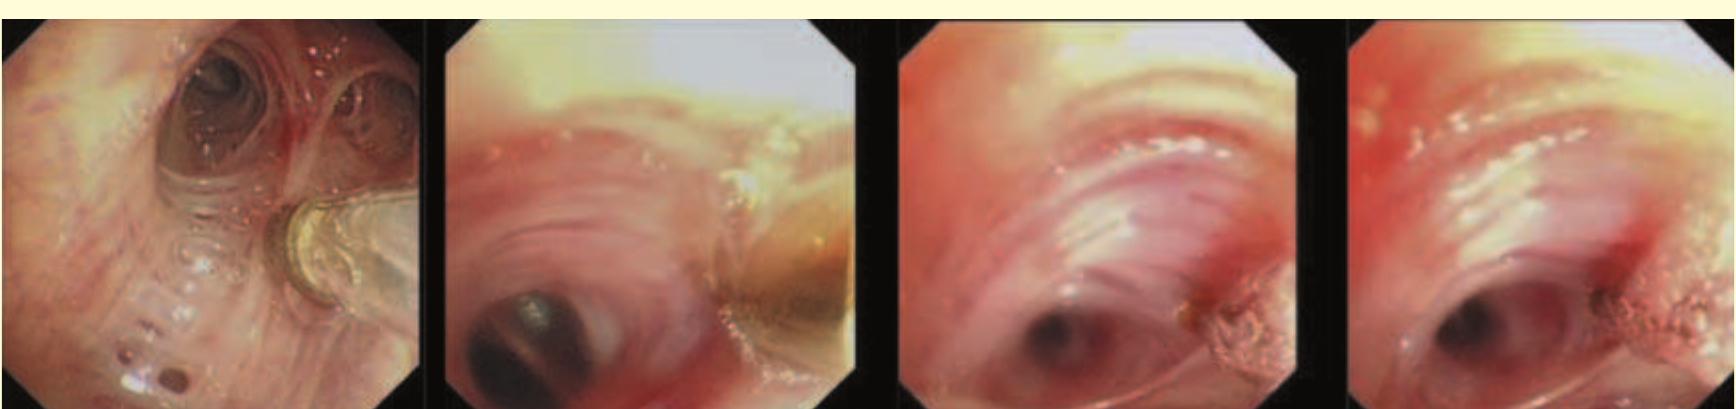

- The bronchoscope is then rotated anticlockwise by 150° to examine the subcarinal lymph nodes (station 7), extending down to the distal margin of the bronchus intermedius.

- Superior to the 11R lymph node, the right upper lobe bronchus and pulmonary artery may be visible.

- Once the loop is tightened around the bronchoscope, the endobronchial blocker can be guided to any lobar bronchus (Fig. 12.11).